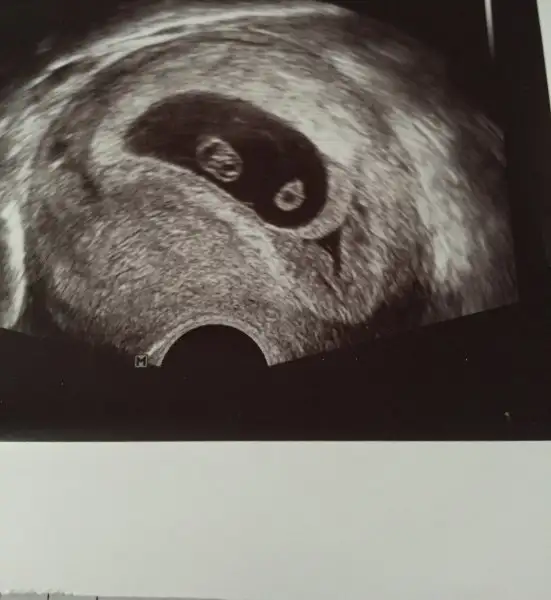

Merhabalar bende yorum alabilir miyim üstten ultrasonla bakıldı tam 6 haftalık görüntüsü bebeğimin

Bbek mi sol tarafindaydi kese mi canim benim kese sol tarafimdaydi en son gittigimde yarinda tekrar gidicrm bakalkm ne olacak buraya paylasirim usg fotosunu heycanla bekliyorum bendeUltrason resmini bilmiyorum da benim sol tarafimdaydi hep ve erkekmis.

Bbek mi sol tarafindaydi kese mi canim benim kese sol tarafimdaydi en son gittigimde yarinda tekrar gidicrm bakalkm ne olacak buraya paylasirim usg fotosunu heycanla bekliyorum bende6+3 gunluk yarin 6+4 olacak ins kalp atisini duyarim

Himm anladim canim benim kese sol tarafimdaydi vajinal usg de sol tarafa yakindi kese vallahi yarin belli olur artik cok heycanliyim ya kalp atisini duyarmiyim acabaBenim sol tarafimdaydi. Ultrason fotografindan bisey anlamadim acikcasi.

Himm anladim canim benim kese sol tarafimdaydi vajinal usg de sol tarafa yakindi kese vallahi yarin belli olur artik cok heycanliyim ya kalp atisini duyarmiyim acaba